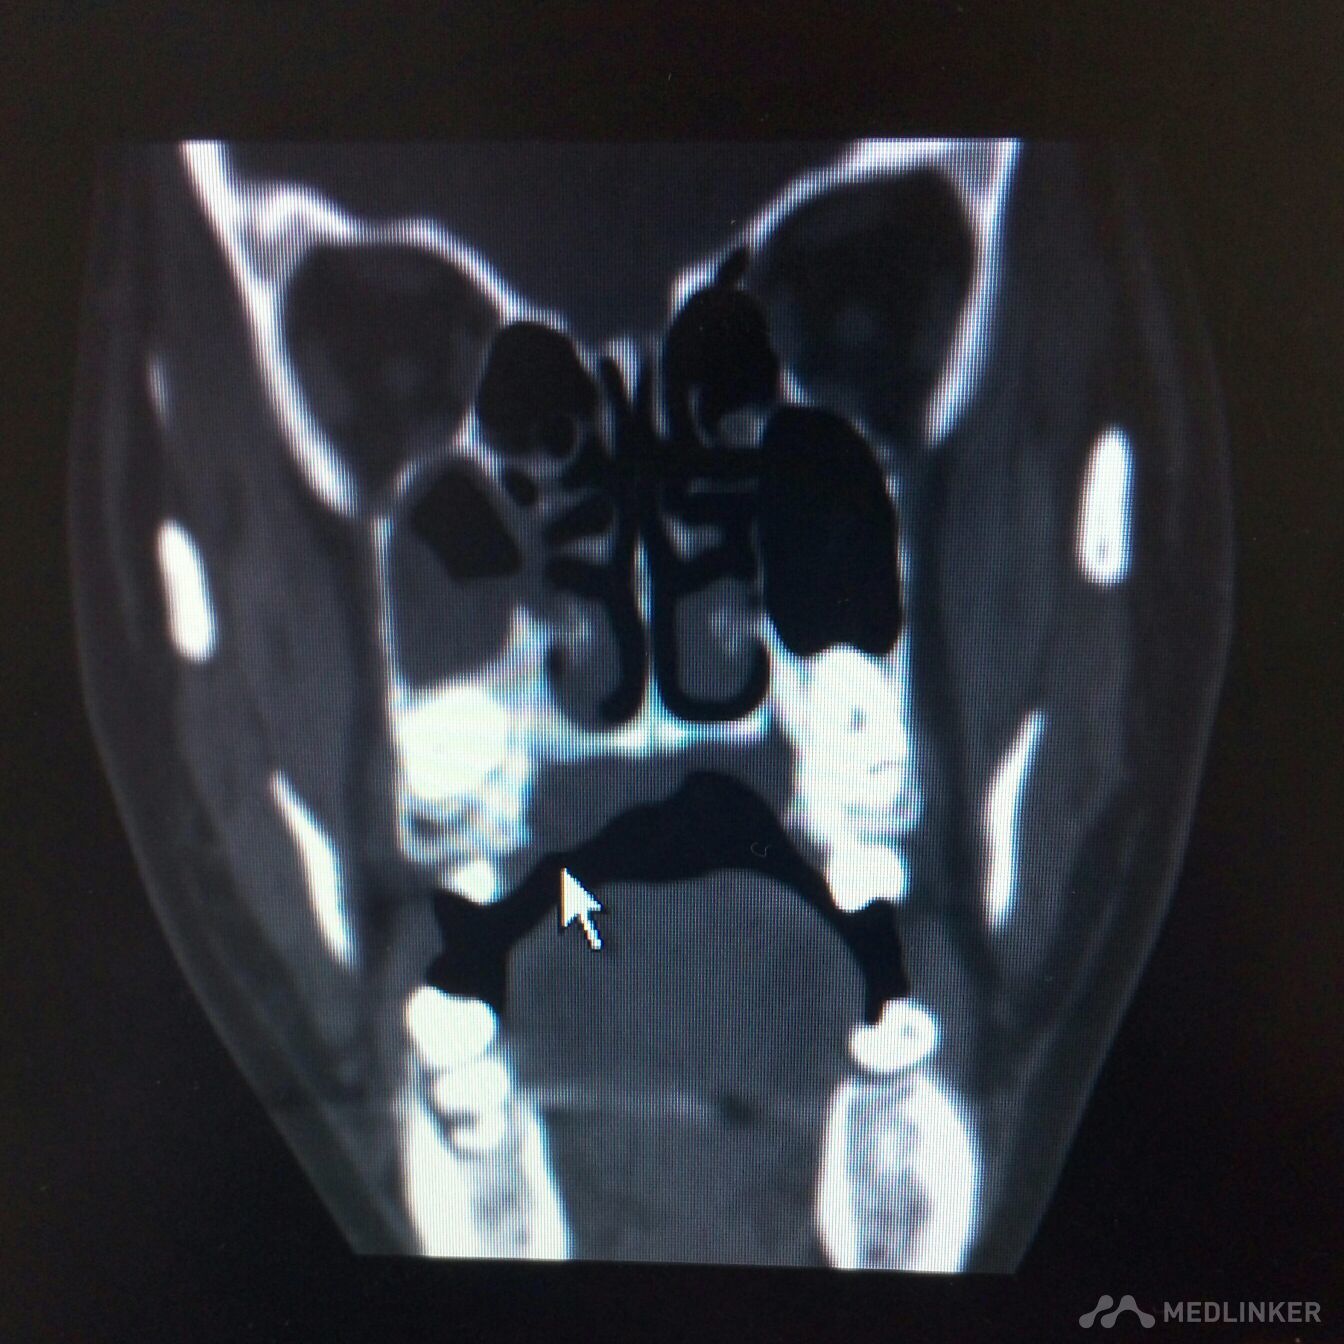

右侧上颌骨肿物,波及上颌窦,鼻腔。手术方案??

患者,女,38岁。因“发现右侧腭部肿痛一周”,来诊。查体:颌面部对称,张口度好。腭部右侧可见粘膜凸起肿物,约2*3cm,近中线处溃烂,有溢脓。CT检查可见肿物突入上颌窦及鼻腔,骨质破坏。现应用抗菌素治疗。拟行病理活检。请同仁看看手术方案?患者年轻,一侧上颌骨去除,假体如何修复?可否请鼻科联合手术,保留颌骨?